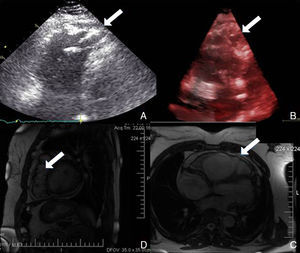

No âmbito da investigação diagnóstica foi realizado eletrocardiograma (ECG) de 12 derivações, que mostrou padrão de bloqueio de ramo direito, conjuntamente com a presença de onda épsilon e inversão das ondas T nas derivações V1 a V3 (Figura 1). Na caracterização das alterações eletrocardiográficas da MAVD foi realizado ECG das derivações precordiais direitas e ECG modificado de Fontaine, este último mediante a seguinte disposição de elétrodos: elétrodo do membro superior direito sobre a área do manúbrio do esterno, elétrodo do membro superior esquerdo sobre a área da apófise xifoide e elétrodo do membro inferior esquerdo na área correspondente de V4, tendo‐se mantido a velocidade de registo a 25mm/s e voltagem a 10mm/mV (Figura 2). Ambos os métodos mostraram uma nítida clarificação das ondas épsilon, em especial neste último (Figura 3 A e B). Procedeu‐se à realização de ecocardiograma transtorácico bidimensional e a três dimensões na nossa instituição hospitalar que mostrou ventrículo direito severamente dilatado e hipocinético, com presença de trabéculas profundas e vários tendões no ápice e dilatações saculiformes na parede livre do ventrículo (Figura 4A e 4B); a ressonância magnética nuclear cardíaca (RMN‐C) mostrou a existência de pequenos focos de infiltração adiposa subepicárdica na parede livre e inferior do ventrículo direito, septo interventricular e parede livre do ventrículo esquerdo; com realce tardio observou‐se a existência de focos de realce intramiocárdico no septo interventricular compatíveis com fibrose (Figura 4C e D).

A realização de ressonância magnética cardíaca nesta situação – e após a realização de ecocardiograma transtorácico na nossa instituição hospitalar – não era obrigatória. No entanto, dada a sua exequibilidade e a existência de possibilidade de constatação das características imagiológicas desta miocardiopatia procedeu‐se à sua realização9.